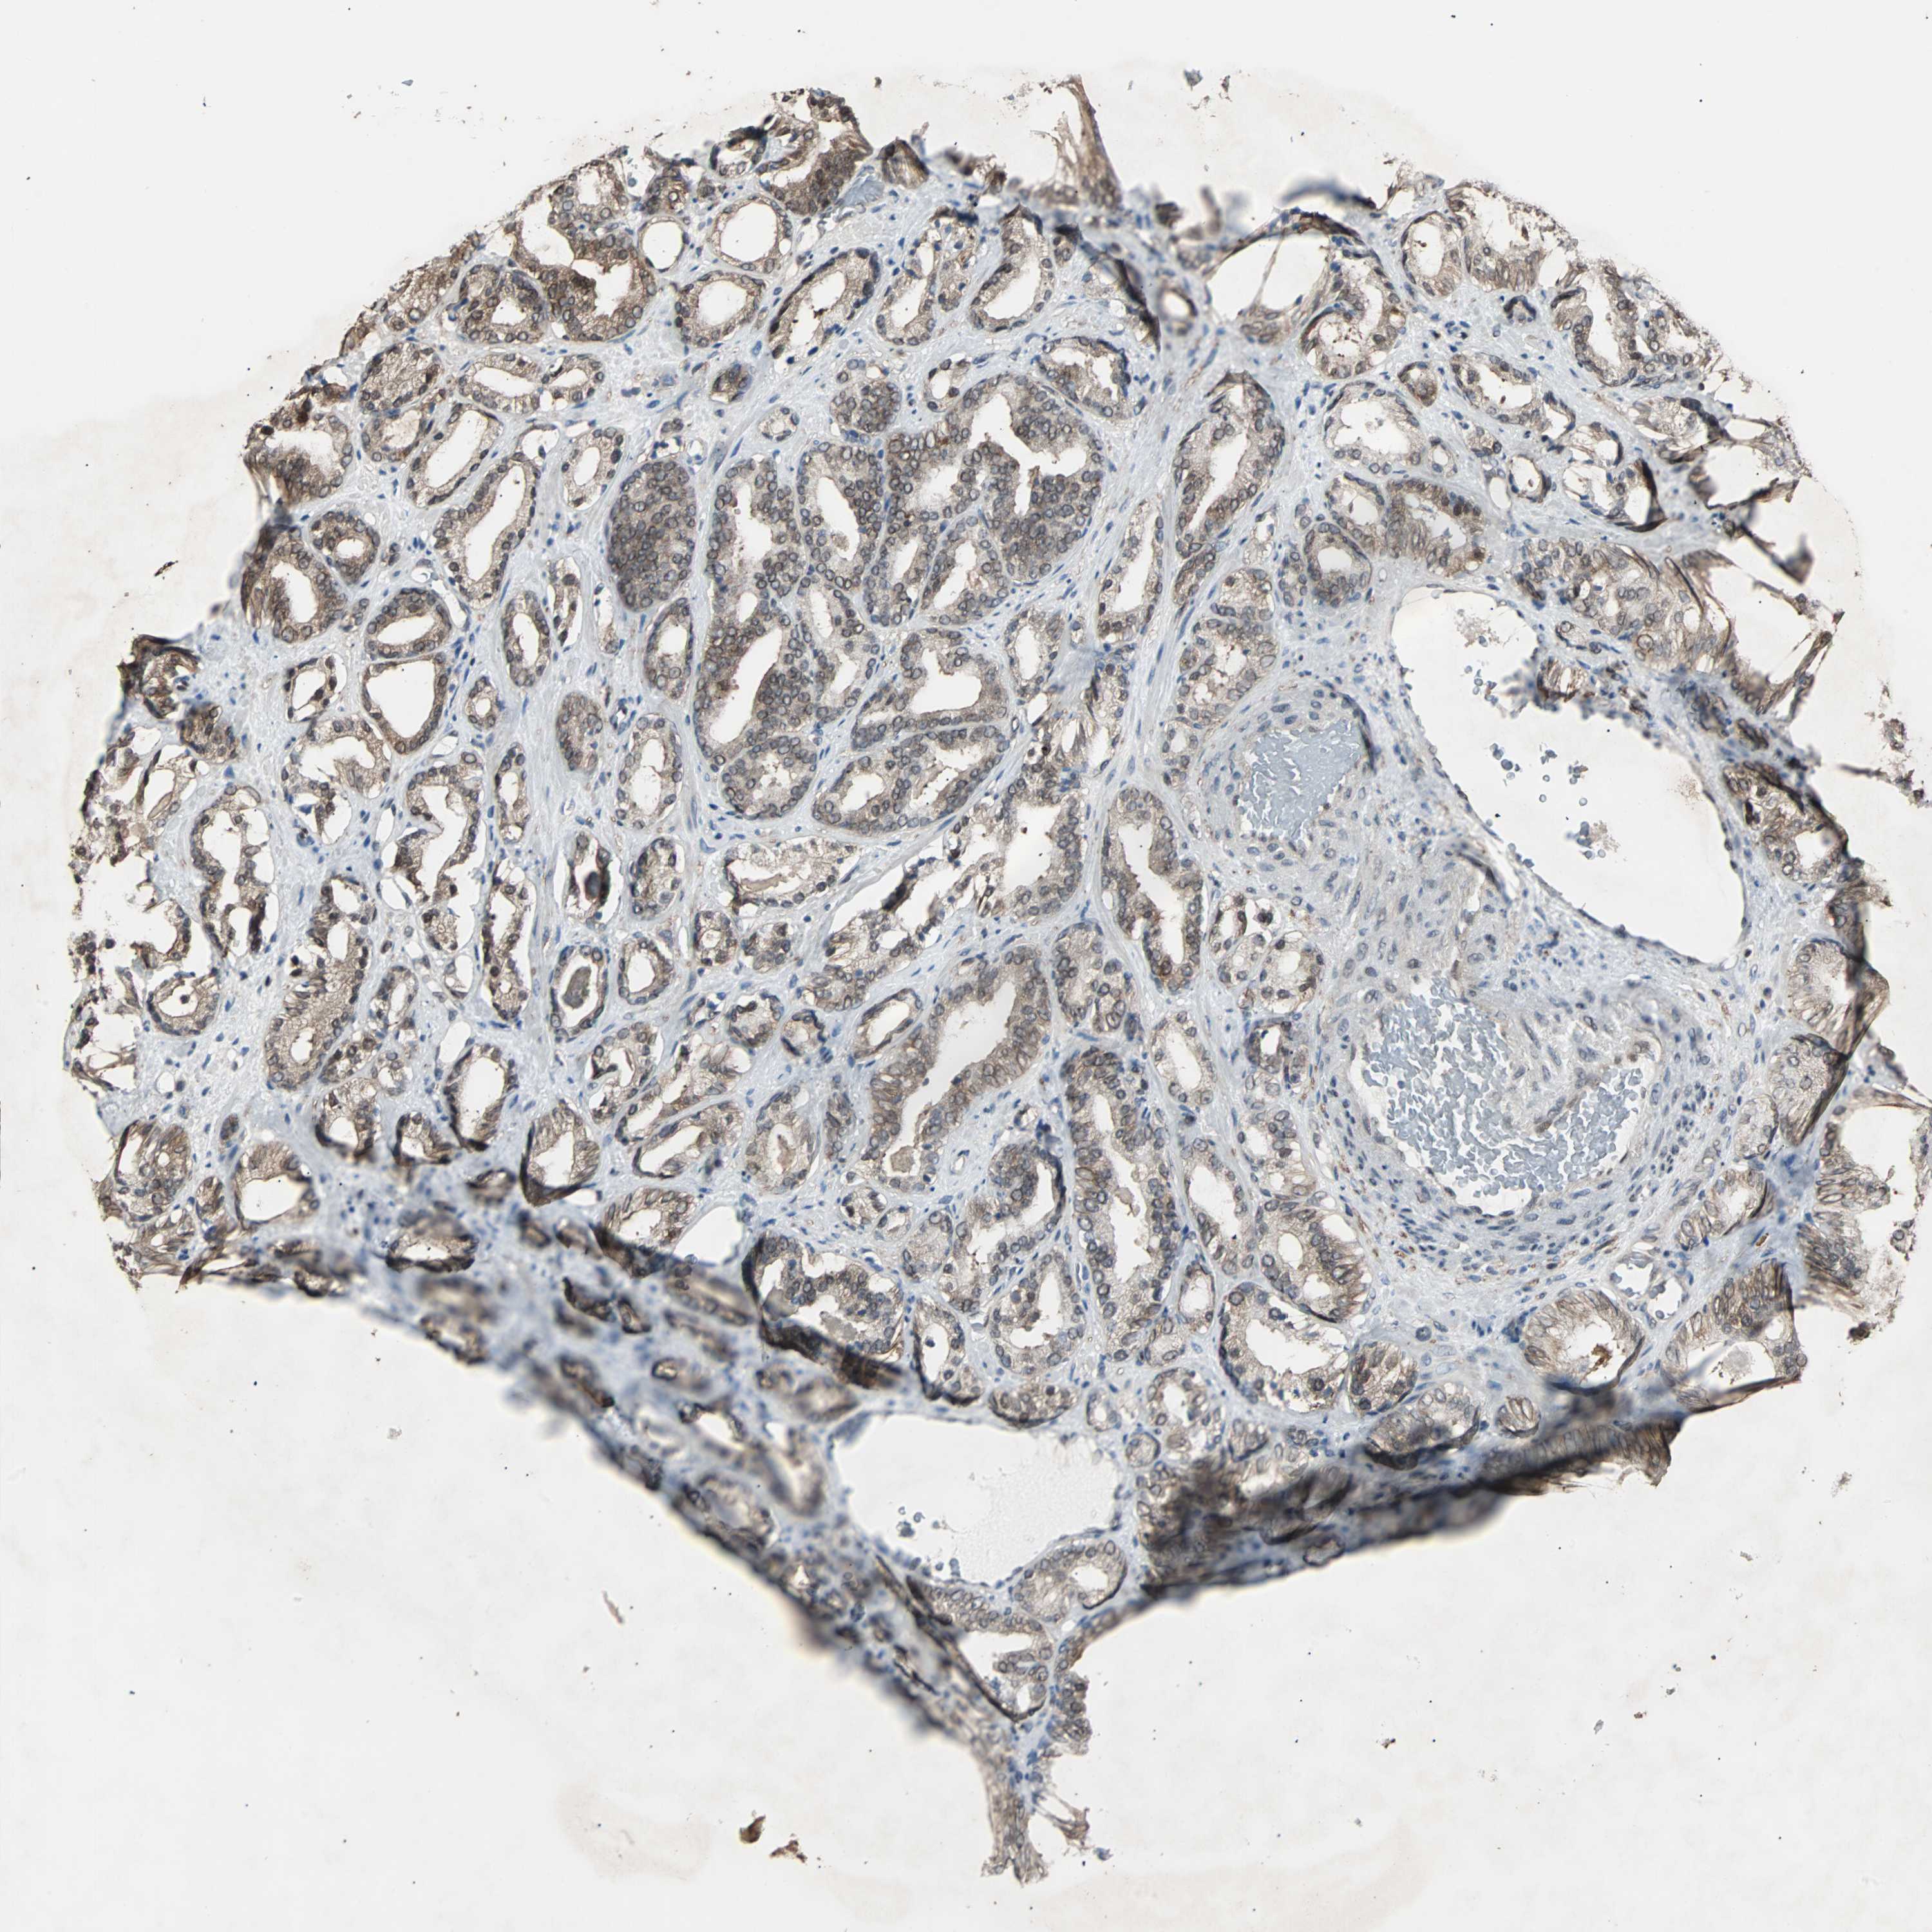

PROSTATE CANCER - Protein expressioni

A mouse-over function shows sample information and annotation data. Click on an image to view it in a full screen mode. Samples can be filtered based on level of antibody staining by selecting one or several of the following categories: high, medium, low and not detected. The assay and annotation is described here.

Antibody stainingi

Antibody staining in the annotated cell types in the current human tissue is reported as not detected, low, medium, or high, based on conventional immunohistochemistry profiling in selected tissues. This score is based on the combination of the staining intensity and fraction of stained cells.

Each image is clickable and will lead to virtual microscopy that enables deeper exploration of all samples and also displays staining intensity scores, fraction scores and subcellular localization as well as patient and tissue information for each sample.

HPA022434

HPA022953

HPA022959

HPA028758

CAB007783

Staining

High

Medium

Low

Not detected

Intensity

Strong

Moderate

Weak

Negative

Quantity

>75%

75%-25%

<25%

None

Location

Nuclear

Cytoplasmic/membranous

Cytoplasmic/membranous,nuclear

Adenocarcinoma, High grade

Adenocarcinoma, Low grade